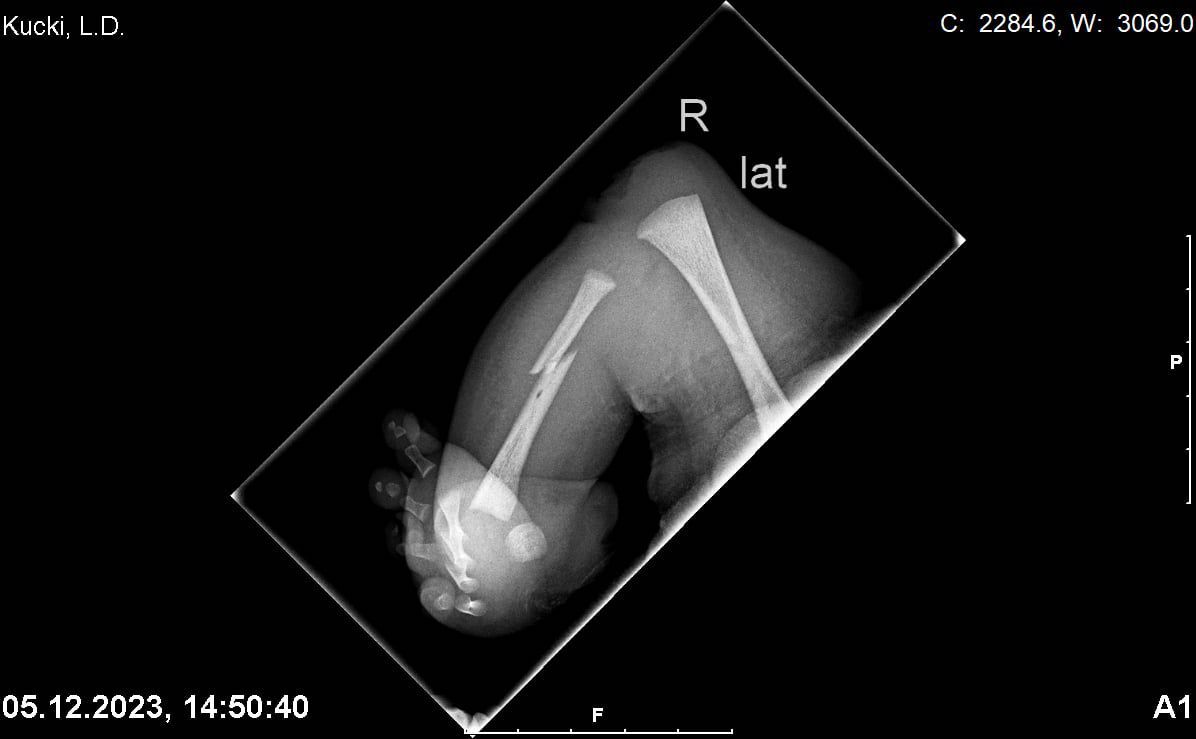

Zdjęcia RTG nóżek po urodzeniu Leo